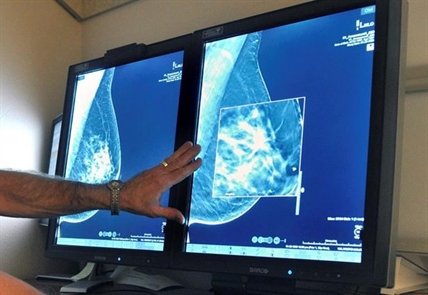

Giving women with very dense breasts an MRI scan in addition to a mammogram led to fewer missed cancers but also to a lot of false alarms and treatments that might not have been needed, a large study found.

About half of women over 40 have dense breasts and about 10% have very dense ones. That raises their risk of developing cancer and makes it harder to spot on mammograms if they do. U.S. regulators are making rules to require that women get breast density information when they have mammograms, and many places provide it now. But what to do if you have dense breasts is unclear — it’s not known if more or different types of screening such as MRIs or ultrasounds help.

The study involved more than 40,000 Dutch women ages 50 to 75 with very dense breasts who had normal results from a mammogram, a screening X-ray offered every two years in the Netherlands. About 8,000 of them also were offered an MRI scan, which uses powerful magnets to create detailed images, and 4,783 women agreed.

The rate of these cancers after two years was twice as high in the group that was only offered mammograms. This suggests that adding MRIs to initial screening did catch more cancers, but they also gave a lot of false alarms— about 80 per 1,000 scans. Three quarters of women who had a biopsy after a questionable MRI turned out not to have cancer.